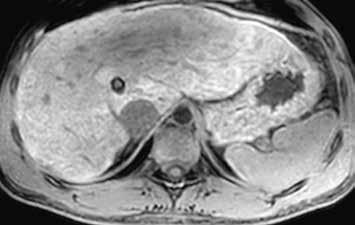

U pacientů s velkými regenerativními uzly vidíme hypervaskularizované ložisko či ložiska, jejichž sycení přetrvává i do portální fáze vyšetření (obr. 13–19). V nativním MR obraze jsou patrná ložiska – v T1-váženém obraze hyperintenzní a v T2-váženém obraze izointenzní či heterogenně intenzní.

Nativně je v jaterním parenchymu naznačeno několik minimálně hyperintenzních ložisek (13). Ložiska se zvýrazňují ve fázi arteriální (14) i portovenózní (15). V hepatospecifické fázi jsou nadále hyperintenzní (16).

Nativně na CT je nezřetelně naznačeno několik hypodenzních ložisek (17). Všechna se vcelku homogenně sytí v arteriální fázi (18). V portovenózní fázi je sycení jater celkově nehomogenní, ložiska jsou však nadále lehce hyperdenzní oproti okolnímu parenchymu jater (19).